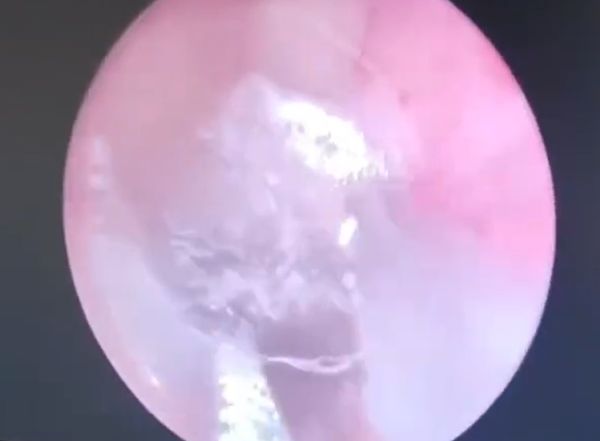

综合陆媒报道,耳鼻喉科医生韩兴龙透过耳内镜检查时,发现女子的耳道满布白色的丝状物,初时以为是霉菌性外耳道炎,他再仔细查看时,越看越不对劲,便着手清除丝状物,耳道里突然钻出一只生物,原来竟是一只蜘蛛。

蜘蛛在女子的耳道内逃窜,韩兴龙花了一番功夫才顺利将它夹住、取出,幸好这只蜘蛛没有毒性,因此女子除了耳道有些损伤以外,其余并无大碍。